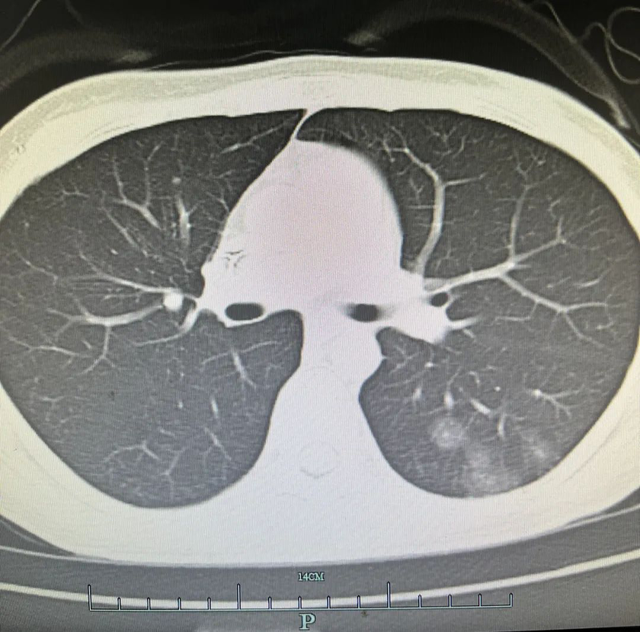

“肺部CT提示双肺有多个结节,部分为磨玻璃影”,王海明结合病史和肺部CT检查,面色有些凝重,“这肺部结节恶性的可能性很大。”

考虑到小杨的身体原因,王海明为她进行了PET/CT检查,结合PET/CT结果,小杨和王海明心中“最坏的猜测”还是被证实了!

“肺部结节考虑为恶性肿瘤”,可小杨只是平静地接受了这个结果,进入外科病区,准备接受进一步的诊治。